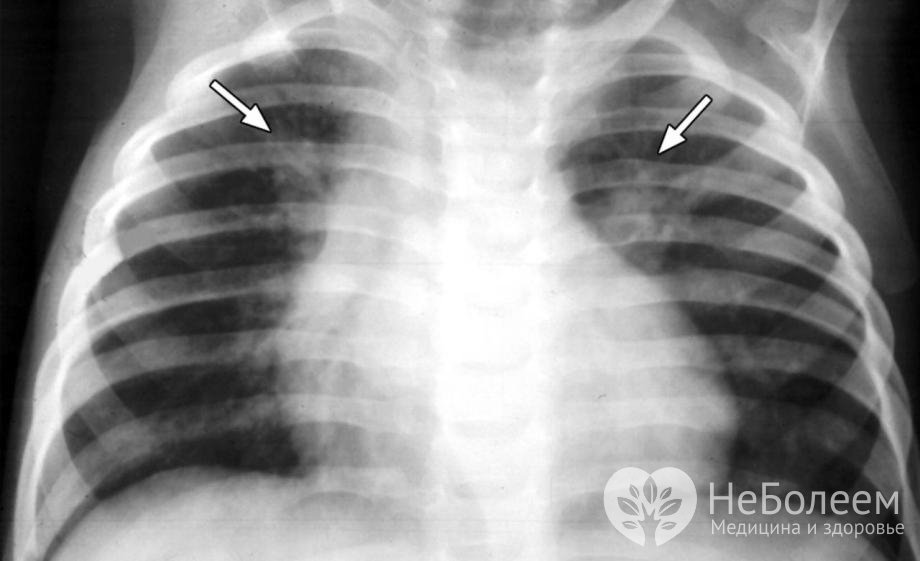

Двухсторонняя пневмония на рентгеновском снимкеВозбудителями двусторонней пневмонии чаще всего выступают грамположительные микроорганизмы. От 40 до 60% случаев заболевания вызываются пневмококками; реже – стафилококками и стрептококками. Иногда возбудителями двусторонней пневмонии оказываются микоплазмы, хламидии, вирусы, грибки и некоторые грамотрицательные бактерии – гемофильная палочка, палочка Фридлендера, энтеробактерии, кишечная палочка, протей, легионелла и пр. Нередко отмечаются случаи смешанных инфекций.

В целях уточнения диагноза проводится рентгенография легких. При поражении паренхимы на снимках просматриваются затемнения различной величины и локализации, смещение плевральных листков и расширение синусов, а в случае распространения воспалительного процесса на интерстициальную ткань – усиление легочного рисунка.

Основной метод диагностики двухсторонней пневмонии – рентгенография легкихОбщий анализ крови показывает повышение СОЭ до 30–50 мм/час и лейкоцитоз с увеличением доли палочкоядерных клеток в лейкоцитарной формуле до 6–30%. Микроскопия и бакпосев мокроты и смывов носоглотки позволяют выявить тип возбудителя и определить чувствительность данного штамма к антибактериальным и антивирусным препаратам.

С целью контроля эффективности терапии на третьей или четвертой неделе заболевания проводится контрольная рентгенография легких. После выписки из стационара пациент в течение года находится на диспансерном учете, проходя периодические осмотры пульмонологом. Два раза в год проводится общий анализ крови, бактериологическое исследование мокроты и флюорография.